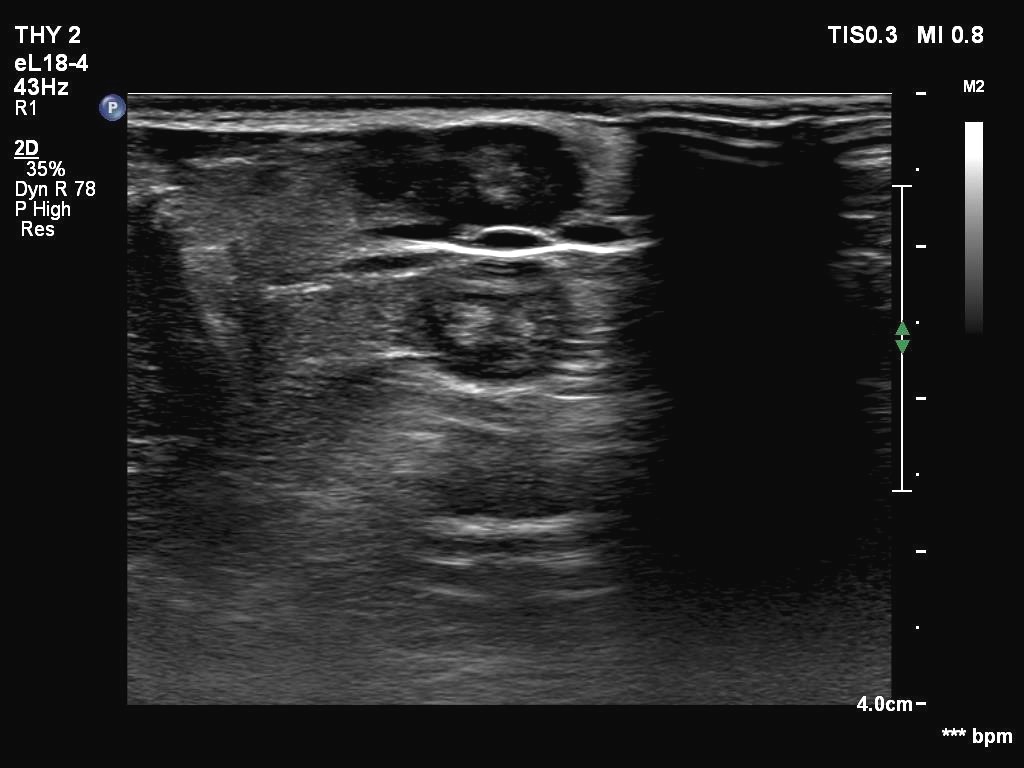

Ultrasonography. The thyroid was echonormal. There were two partly deeply hypoechoic nodules, one in the ventrolateral part of the right lobe and another one in the isthmus. Both had irregular margins and punctate echogenic foci. There was a mirror image artifact of the lesion in the isthmus.

Both nodules had multiple suspicious features: beside deep hypoechogenicity and irregular borders, microcalcifications should be also considered. The nodule in the right lobe presented also three possible sonographic signs of a possible extrathyroidal spread: the pseudocapsule of the thyroid was not intact, the lesion had both abutting and butting contours.

According to the literature, the mirror image artifact is not an exceptional finding. Nevertheless, such a reflection very similar to the original is quite rare. The prerequisite of this phenomenon is the flattening of the trachea' wall as is observed in this case. The explanation is as follows: 'The primary beam reflects from such a surface (e.g. diaphragm) but instead of directly being received by the transducer, it encounters another structure (e.g. a nodular lesion) in its path and is reflected back to the highly reflective surface (e.g. diaphragm). It then again reflects back towards the transducer.' (Source: radiopedia.org.)